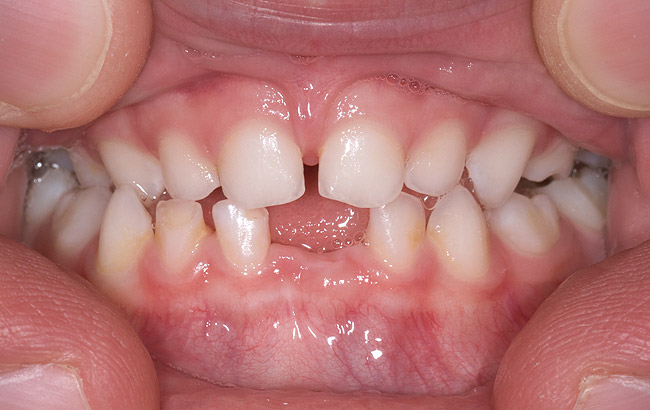

(14.) Angle Class III occlusion with constricted maxilla.

Figure 14